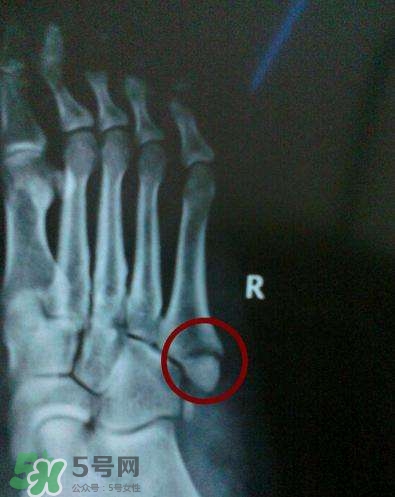

骨裂是骨折的一種,臨床上嚴(yán)格來(lái)說(shuō)沒(méi)有骨裂這個(gè)說(shuō)法, 骨裂只是普通的說(shuō)法,是骨折的輕微狀態(tài),也就是骨頭裂開(kāi)了,但是沒(méi)有移位,骨頭之間對(duì)位對(duì)線(xiàn)都是好的,所以一般不需要復(fù)位,只需要固定就可以,而骨折是一大類(lèi),包括沒(méi)有移位的骨折,也包括有移位的骨折。

一般骨裂分為移位骨裂和無(wú)移位骨裂、關(guān)節(jié)內(nèi)骨裂和關(guān)節(jié)外骨裂,一般骨裂4-6周軟骨愈合,3月以上骨性愈合,不愈合的很少見(jiàn),但是畸形愈合的較多見(jiàn)。但是這也不是絕對(duì)的,需要看骨裂的具體的部位損傷的程度。